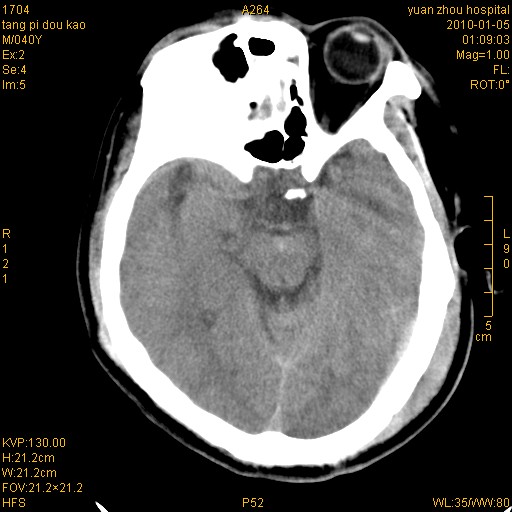

标题: CT23986:M 40Y 外伤数小时 [打印本页]

标题: CT23986:M 40Y 外伤数小时

挫伤血肿形成   还有一个左枕部硬膜外血肿考虑

1)左侧颞枕部硬膜外血肿。2)右侧额部硬膜下血肿。3)双侧额叶及右侧基底节下部脑挫裂伤。4)蛛网膜下腔出血。5)脑水肿。6)左侧前组筛窦及左侧额窦炎症。

+左侧颧骨骨折。

左侧颧骨骨折